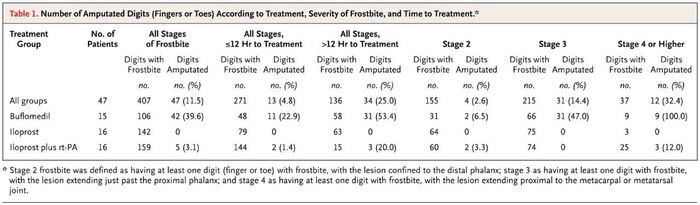

В общей сложности пострадавшая от обморожения провела в больнице 49 дней. Периодически даже впадала в кому. Но это мелочи по сравнению с возможными в таких ситуациях последствиями. Ведь при длительном воздействии низких температур замедляется кровоток. Ткани и органы испытывают кислородное голодание. Потеря пальцев, носа, ушей в таких ситуациях – обычное дело. А в более серьёзных случаях всё заканчивается ампутацией конечностей.